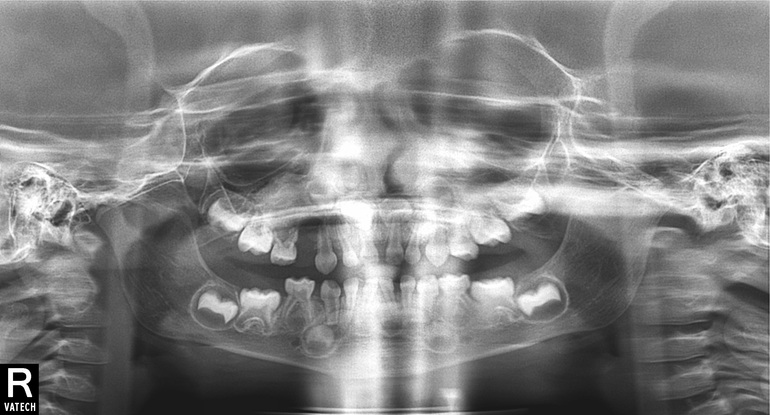

Сходили в субботу на прием в планую клинику, там нам сделали прицельный снимок. Сказали, что это лезет пятерка, а вылезший зуб - это следующий. (у нас такое уже было, что зубки прорезались не по порядку). Сказали, что ничего страшного нет, лечить это не нужно.Но зуб лезет не правильно, под углом, коронкой в щеку. Так же врача смутило, темное пятно между прорезающимся зубом и резцом. Отправила нас на панорамный снимок, после сказала, что они не информативны и нужно еще раз приехать, делать прицельные. на панорамных снимках картина примерно та же, (могу переслать если нужно). Только я белых точечек там не увидела. Только темное пятно.

На приеме говорила что то, что это может быть киста, или какие скопления закладки зубов, я не очень запомнила термины. Очень волнуюсь по этому поводу.